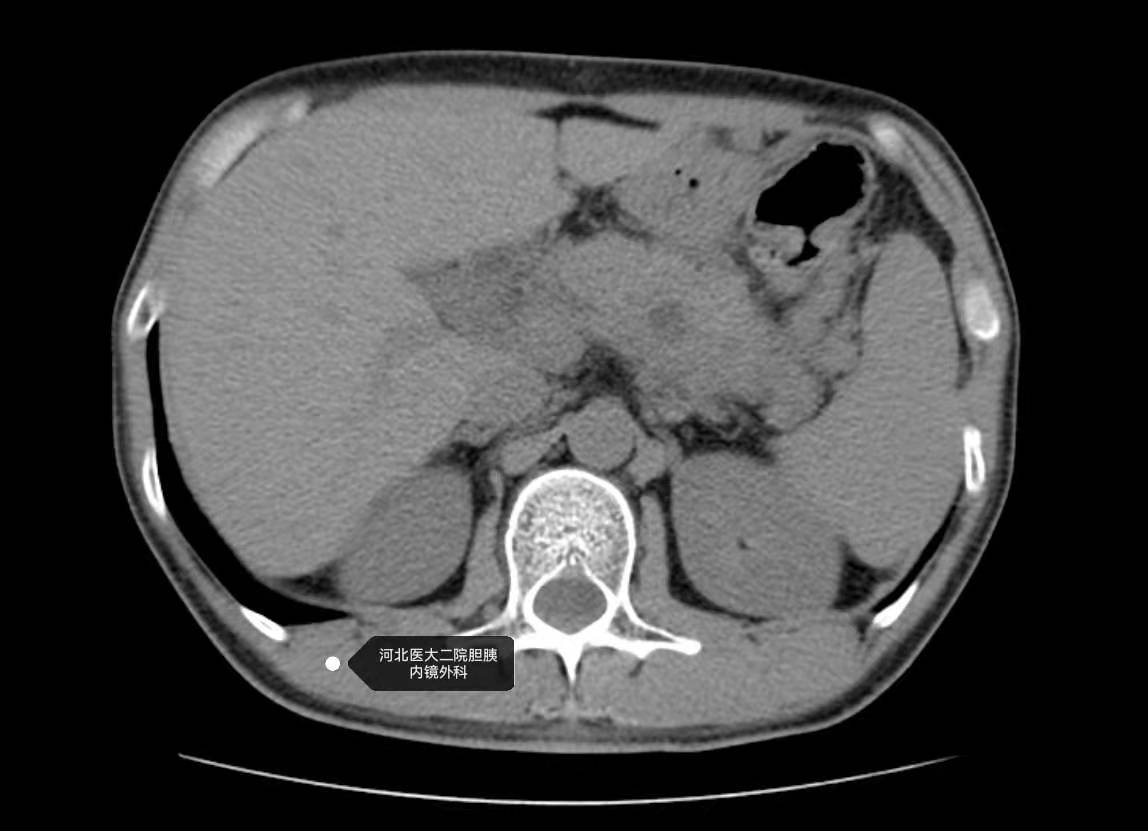

不说病史的情况下,只有下面平扫CT资料,EUS如何判断胰腺占位是个啥性质?

患者青年男性,既往急性胰腺炎病史,且形成了假性囊肿,我们做过EUS引导下的假性囊肿穿刺引流。这次是复查。因为术前考虑诊断比较明确,这个病变就是一个坏死包裹,所以也没有查增强CT或者核磁之类的。